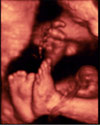

Ecografía 4D del tercer trimestre: Manos y pies de un feto

Ecografía 4D de las manos y pies de un feto en el tercer trimestre de embarazo

La curiosa imagen ecográfica en rotación de este bebé nos muestra claramente sus extremidades superiores y inferiores. De una de las manos podemos contar hasta las falanges. También se observa parte de la cara y del cordón umbilical, que rodea uno de los pies.